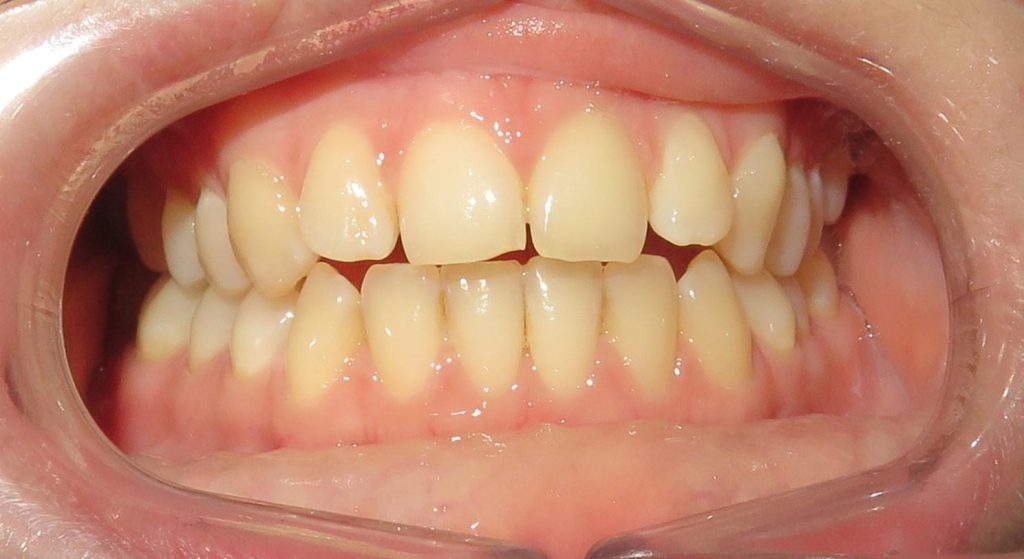

Aby osiągnąć taki efekt, musieliśmy przeprowadzić ekstrakcję złamanej górnej jedynki i w jej miejsce jednoczasowo wszczepić implant, a następnie na pozostałe zęby wykonać licówki i korony pełnoceramiczne w najjaśniejszym odcieniu.

Całość została zaprojektowana w harmonii z twarzą i rodzajem uśmiechu naszej Pacjentki. Leczenie trwało 3 miesiące.

Wykonał je lek.stom. Michał Badowski we współpracy z laboratorium Dentalscan (tech.dent. Joanna Gancarz).